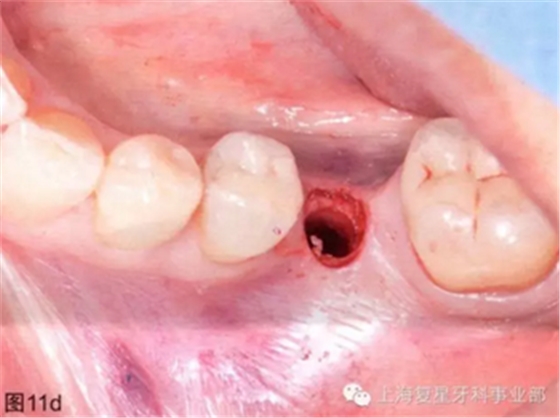

隨后拆除外科導(dǎo)板并檢查制備的種植窩(圖11d)。然后將導(dǎo)板重新定位,將種植體安裝在4.6毫米的種植體攜帶器和手機上(圖11e)。

圖11d:去除外科導(dǎo)板后,制備完成的種植體窩